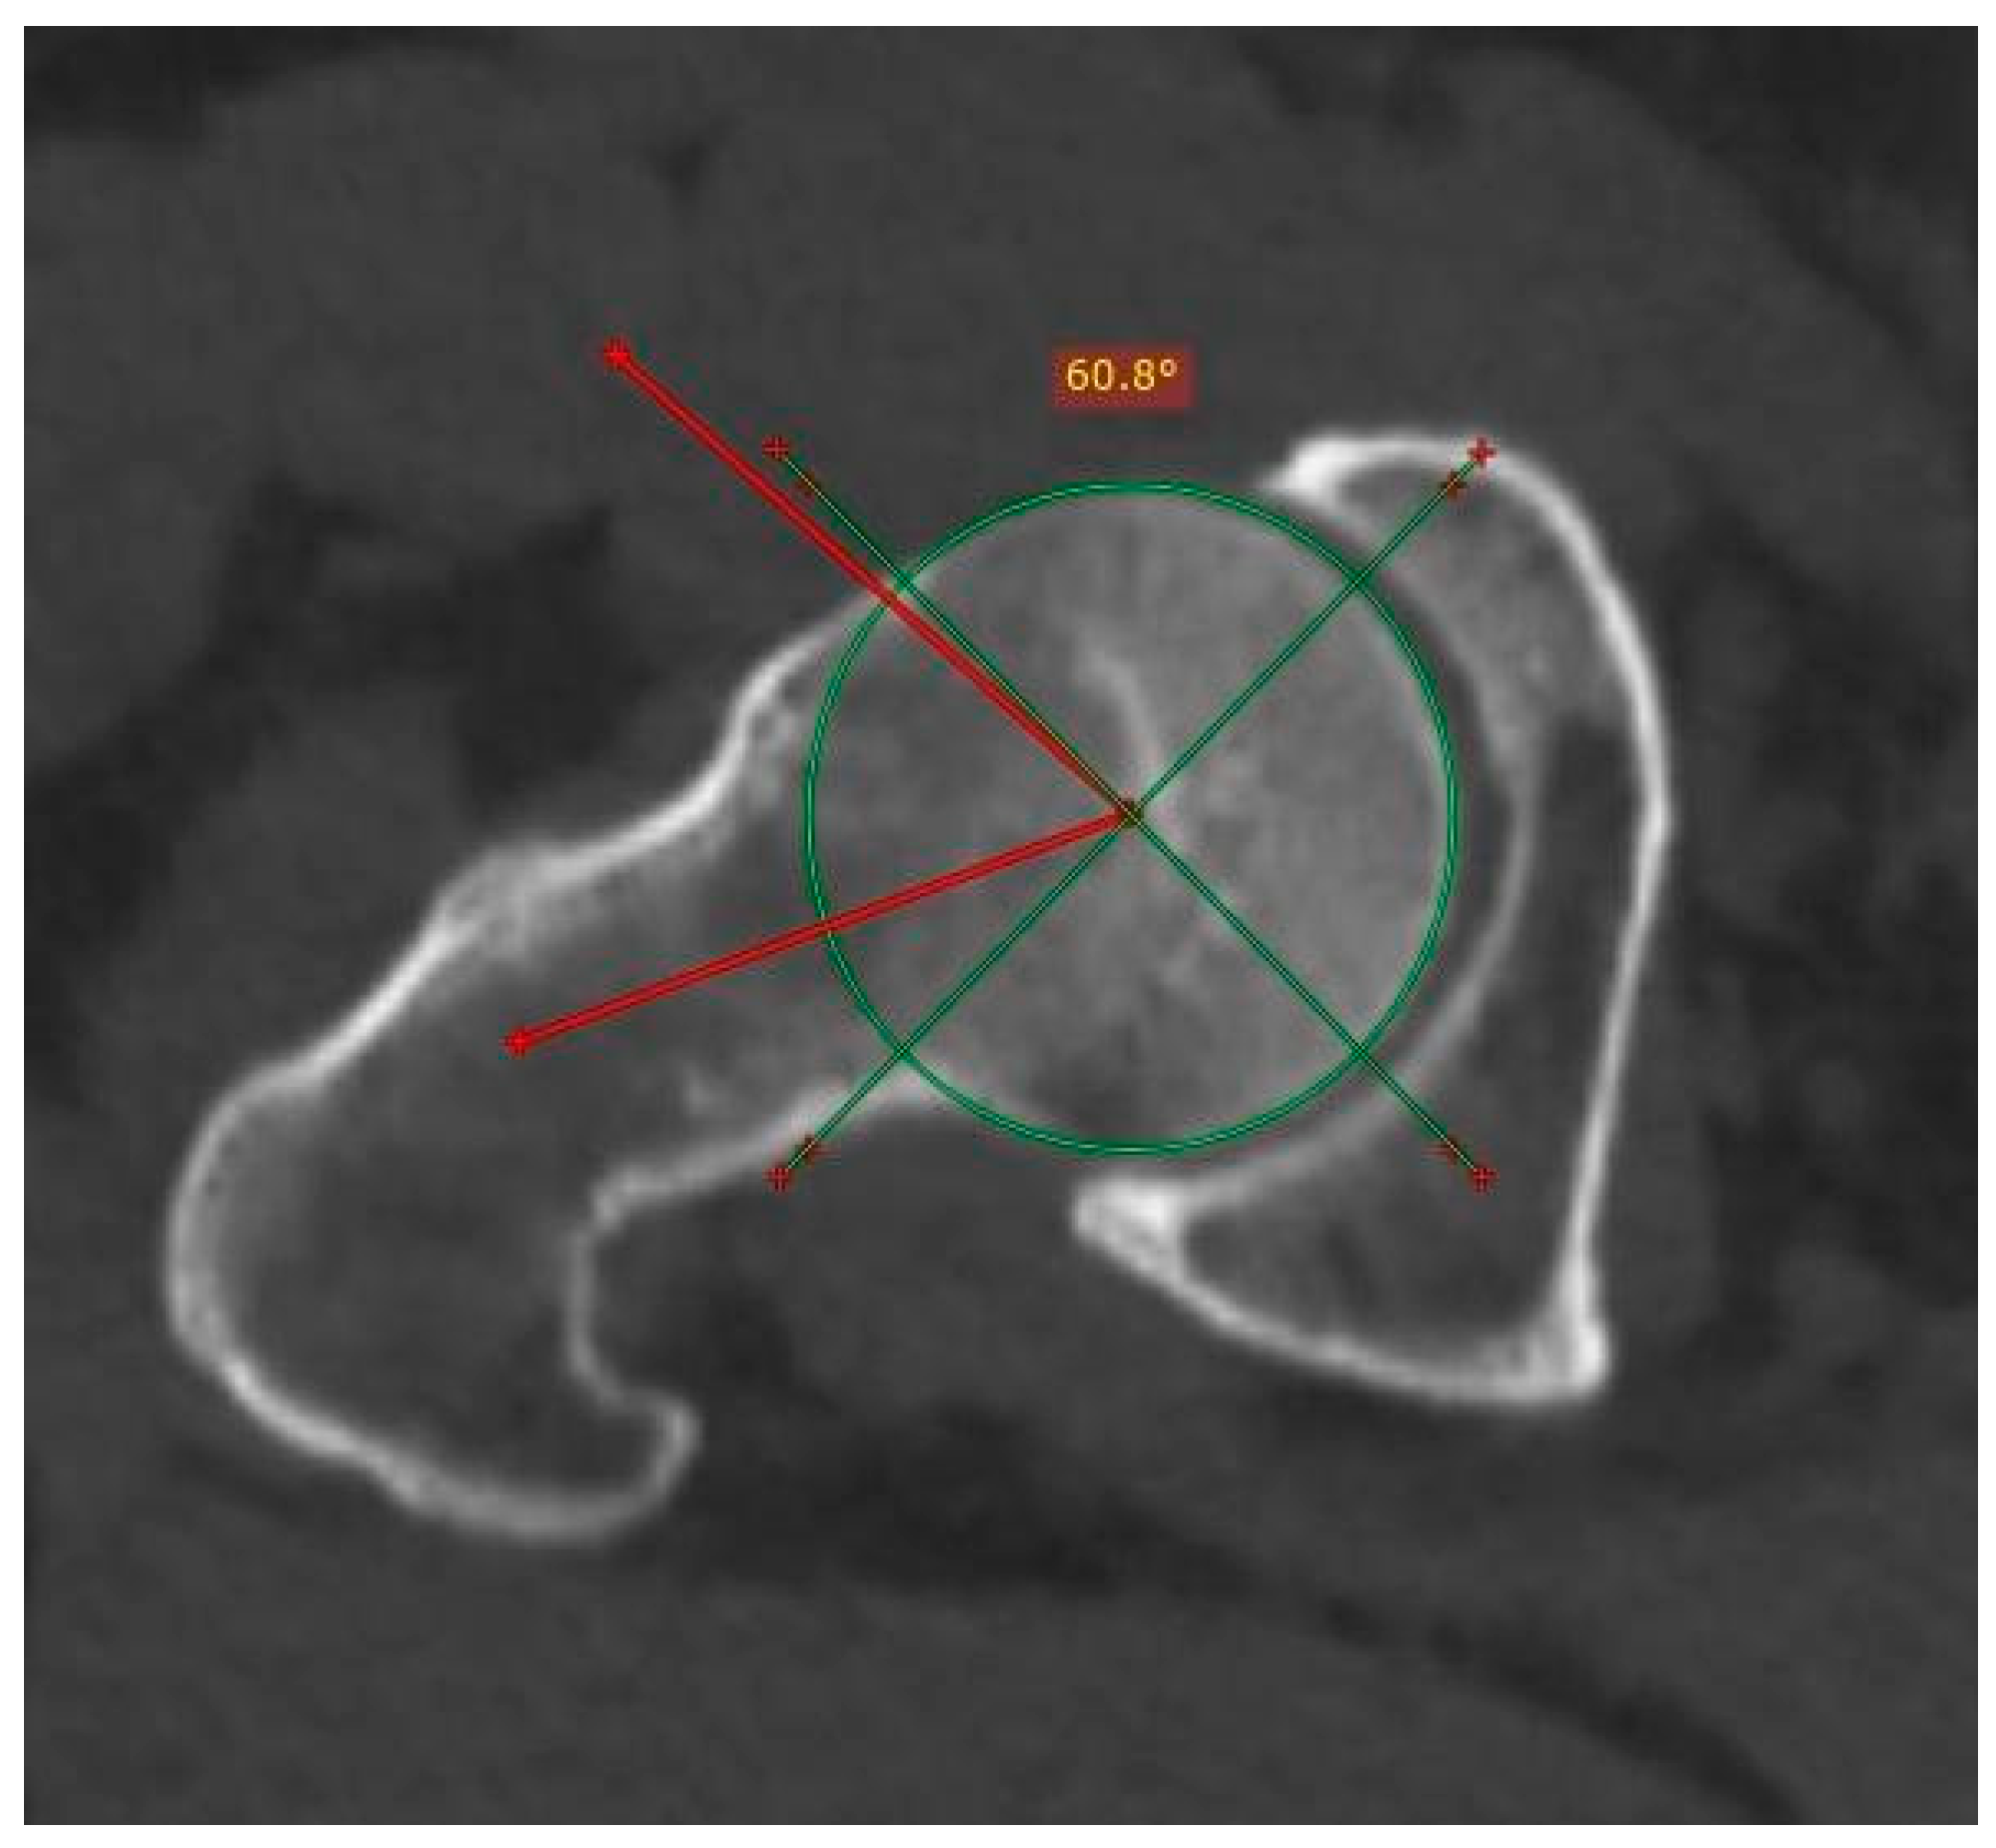

Patients who had compressive symptoms more often presented with C-sign, mixed impingement with 16.66% differences in Wiberg’s angle in patients with and without C-sign; furthermore, the average of the angles was greater in patients with C-sign, with a difference of 0.8112 degrees in the right angle and an even more pronounced difference between the averages of the left angle, at 2.7715 degrees (measurement of the Wiberg angle is depicted in Figure 3).

Figure 3.

Measurement of the center-edge angle (Wiberg) in an asymptomatic patient. An angle is obtained starting from the center of the femoral head, with a stroke following the vertical axis of the same (90°) and the lateral edge of the acetabulum. The normal value is less than 40°.